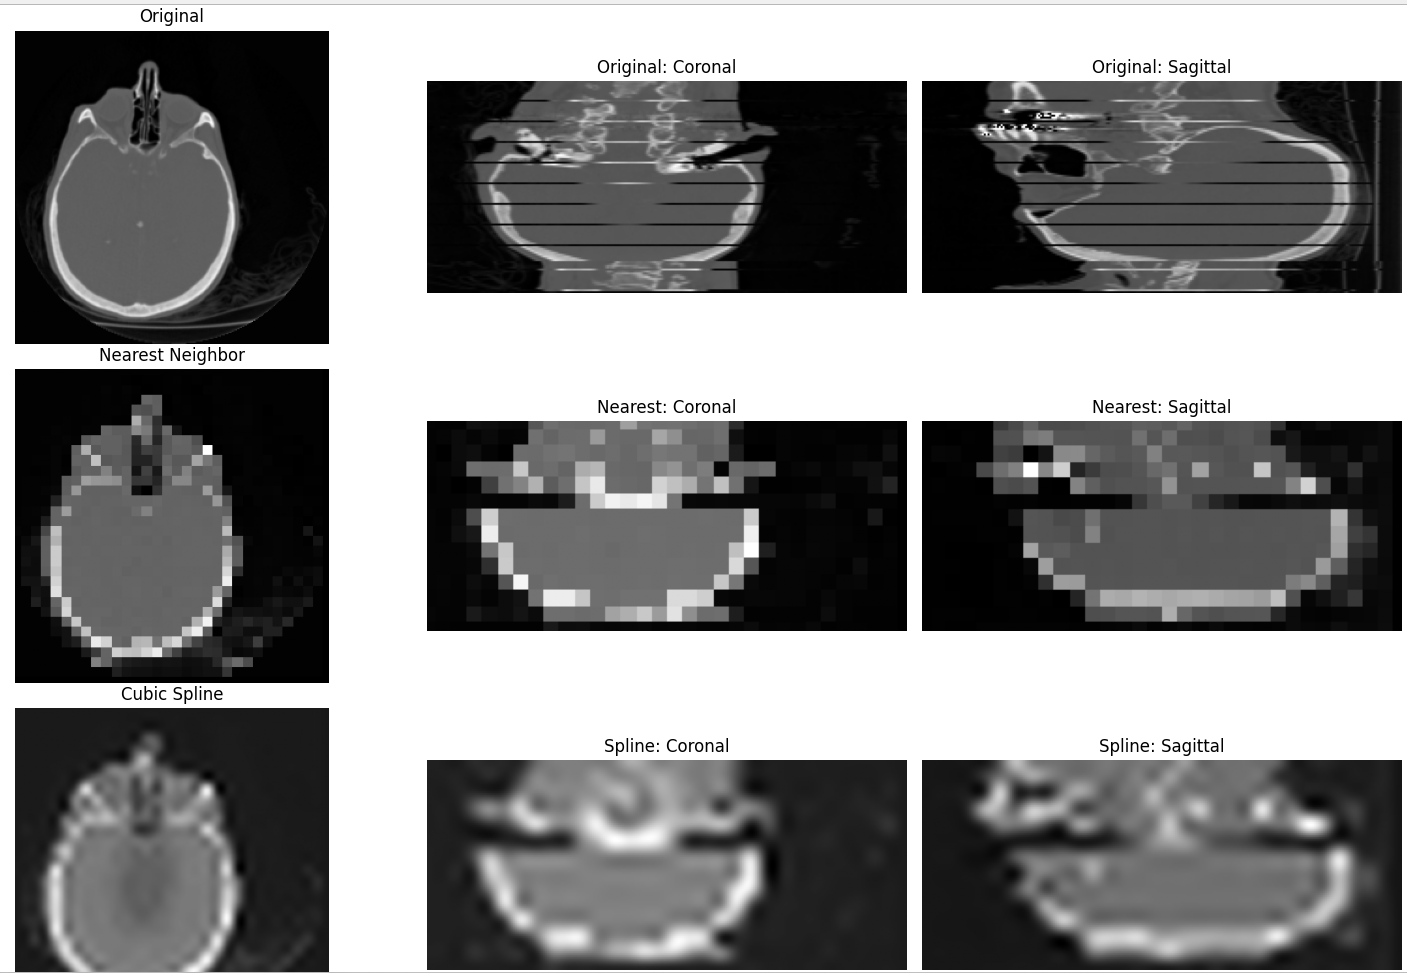

補間は、離散的なデータ点の間を滑らかにつなぎ、解像度を変更する処理である。本プログラムでは、データを1/8に縮小した後、8倍に拡大して元サイズに戻す。最近傍補間(order=0)と3次スプライン補間(order=3)の結果を比較する。

上段に元画像、中段に最近傍補間、下段に3次スプライン補間を表示する。最近傍補間ではブロック状のギザギザが目立ち、スプライン補間では滑らかに復元されている。